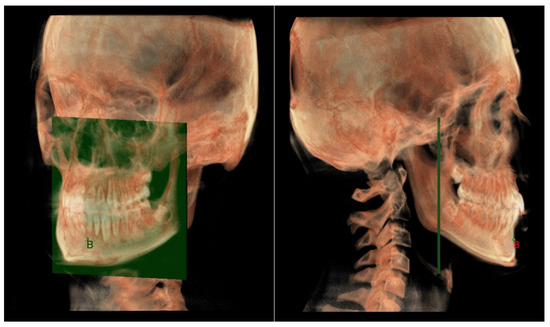

- Maxillary and Mandibular skeletal arches (Figure 1): this parameter compares the lengths of the maxillary and mandibular skeletal arches. The maxillary skeletal arch was measured by the distance between A point and PM, in parallel with Ref. The mandibular skeletal arch was measured by the distance between the orthogonal projection of B point on Ref and ARa, at its intersection point with Ref.

- The mandibular skeletal arch (Figure 7) was measured from the point B to a plane passing through the two lingual tuberosity and normal to the axial plane